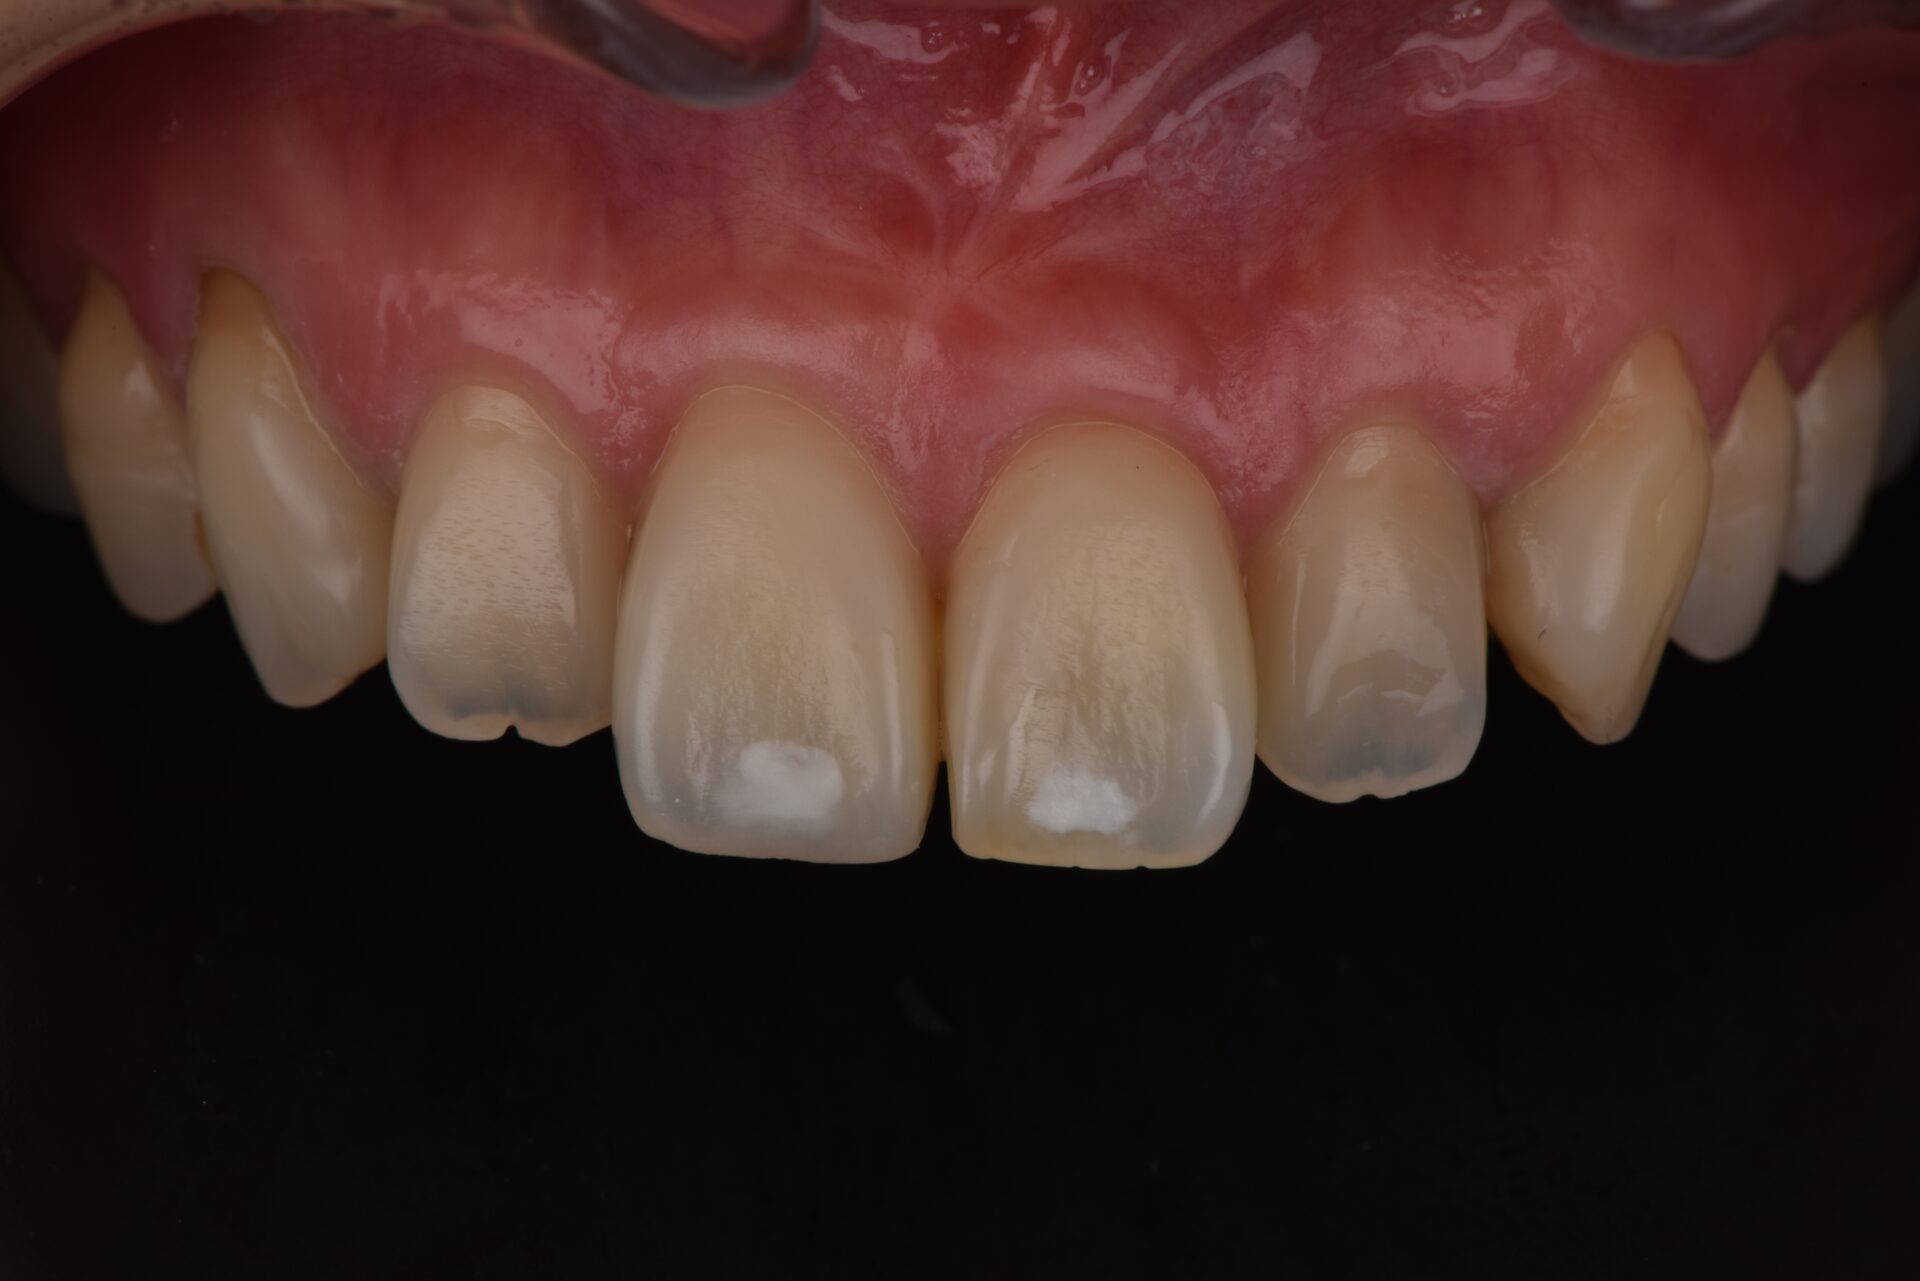

CTG(結合組織移植術) 臨床例②

矯正治療後、下顎前歯部の歯肉が退縮して歯根が露出し、見た目と機能の両面でお悩みでした。歯肉は非常に薄く、付着歯肉も不足しており、ブラッシング時に傷つきやすく、清掃が困難な状態でした。そのため、炎症を繰り返しており、審美的にも不均衡が見られました。長期的に歯周組織を安定させるには、外科的な介入が必要と判断しました。

術前